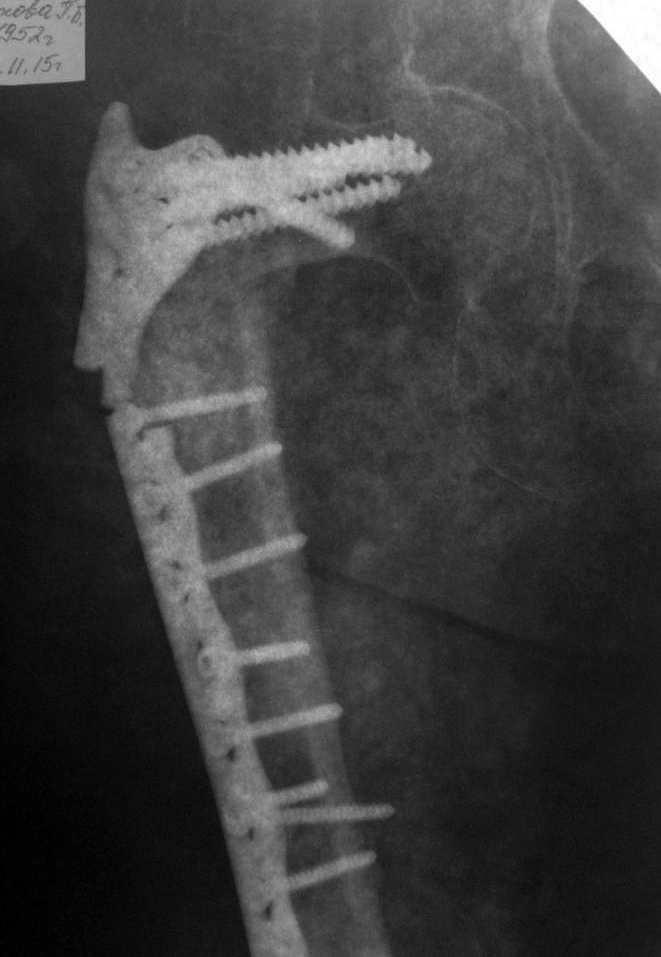

Травма в январе 2013г, тогда же оперирована по поводу чрезвертельного

перелома бедра DHS (снимки отсутствуют). Зимой 2014-2015 без повторной

травмы - перелом металлоконструкции и предположительно, повторный

перелом бедра, повторная операция, с помощью металлоконструкции видимой

на снимках (снимки послеоперационные отсутствуют).

3 недели тому - при сгибании бедра (стригла ногти) почувствовала хруст,

выраженный болевой синдром, потеря опороспособности, рентгенологическая

картина представлена.